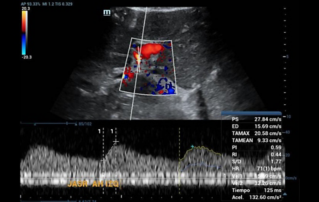

![evaluate-liver-graft-contrasted-ultrasound.thumb.319.319 Ultrasound Journal 37 - Evaluation of liver graft by contrasted ultrasound and variables that may alter normality]() Ultrasound Journal 37 - Evaluation of liver graft by contrasted ultrasound and variables that may alter normalityDiscover how Mindray Resona R9 with Chrono-Parametric Mode CEUS revolutionizes post-liver transplant monitoring, enabling early detection of vascular complications and standardized perfusion assessment.Ultrasound Cases | Ultrasound | Smart applications | Digitalization | General imaging 2025-08-11

Ultrasound Journal 37 - Evaluation of liver graft by contrasted ultrasound and variables that may alter normalityDiscover how Mindray Resona R9 with Chrono-Parametric Mode CEUS revolutionizes post-liver transplant monitoring, enabling early detection of vascular complications and standardized perfusion assessment.Ultrasound Cases | Ultrasound | Smart applications | Digitalization | General imaging 2025-08-11 -